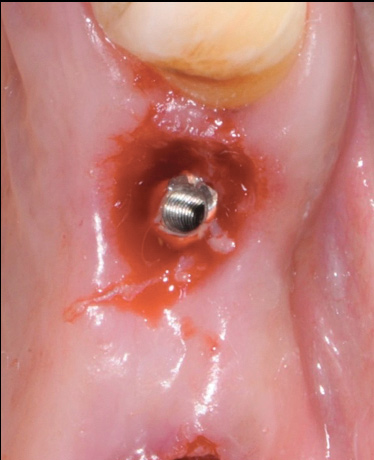

Fig 9. Treatment of peri-implant mucositis: plaque accumulation and mucosal inflammation.

Figure 9

Fig 10. Traumatic impingement of the pontic on the peri-implant mucosa.

Figure 10

Fig 11. After thorough mechanical debridement and modification of the prosthesis to allow cleansing.

Figure 11

An important aspect of both professionally and patient-administered plaque removal is the cleanliness of the implant-supported restoration. A cohort study on 23 patients demonstrated that 74% of implants had no accessibility to proper oral hygiene and 48% of implants presenting with peri-implantitis were those that were not cleansable.17 The non-fitting or non-cleansable overhanging prostheses, therefore, should be considered iatrogenic factors that contribute to the development of peri-implantitis. Similarly, incorrectly positioned implants or foreign bodies such as impression material or excess luting cement can contribute to increased biofilm accumulation and hence favor the development of peri-implant diseases.10 Correction or elimination of these factors (eg, prosthesis removal and adjustment/replacement, if necessary) should be a principal component of the treatment of peri-implant mucositis (Figure 9 through Figure 11).